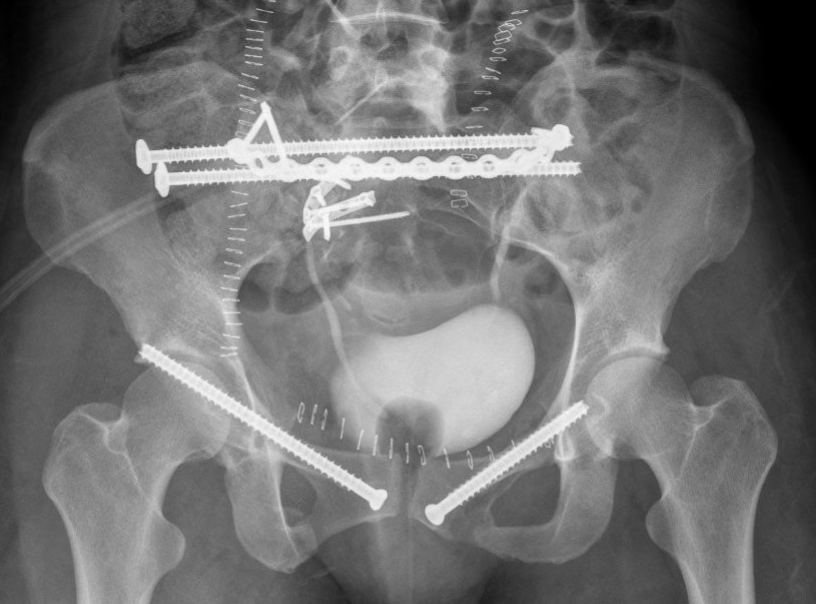

Verticla shearLumbosacral fixation

Lumbosacral fixation with SI screw - triangular osteosynthesis

Vert shear CTVertical shear fixation

Sacral plate, sacroiliac screws, ramus screws

Anterior stabilisation

Pubic symphysis plates

Percutaneous ramus screws